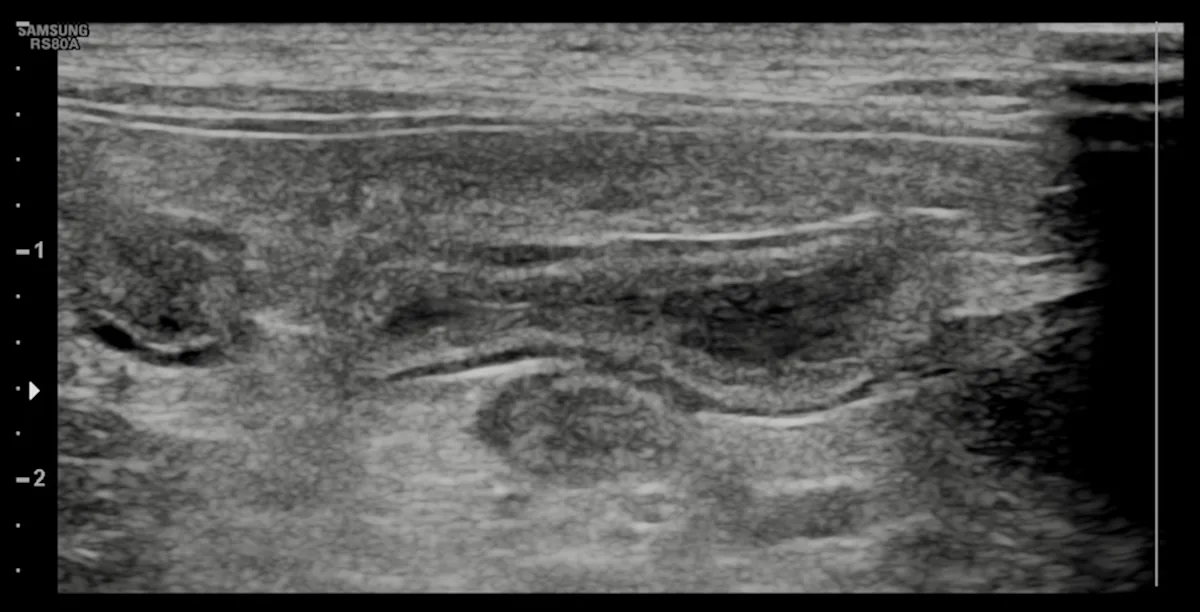

An over-the-needle jugular catheter was placed and blood was collected for an emergency database and venous blood gas. Results revealed hypokalemia (2.6 mEq/L; reference interval, 3.6-4.6 mEq/L), hypoglycemia (64.8 mg/dL; reference interval, 88-130 mg/dL), mild anemia (PCV 21%; reference interval, 29%-35%), and hypoproteinemia (total solids, 4.5 g/dL; reference interval 5.0-6.0 g/dL). Blood smear evaluation was suggestive of leukopenia. A 0.5 g/kg dextrose bolus IV was adminstered, followed by a 20 mL/kg IV bolus of a balanced isotonic crystalloid fluid. A fecal parvovirus antigen test confirmed parvoviral enteritis. An abdominal ultrasound was performed and findings were suggestive of enteritis (Figure 2).

Abdominal ultrasound demonstrated no evidence of small intestinal obstruction or intussusception; findings were suggestive of enteritis.